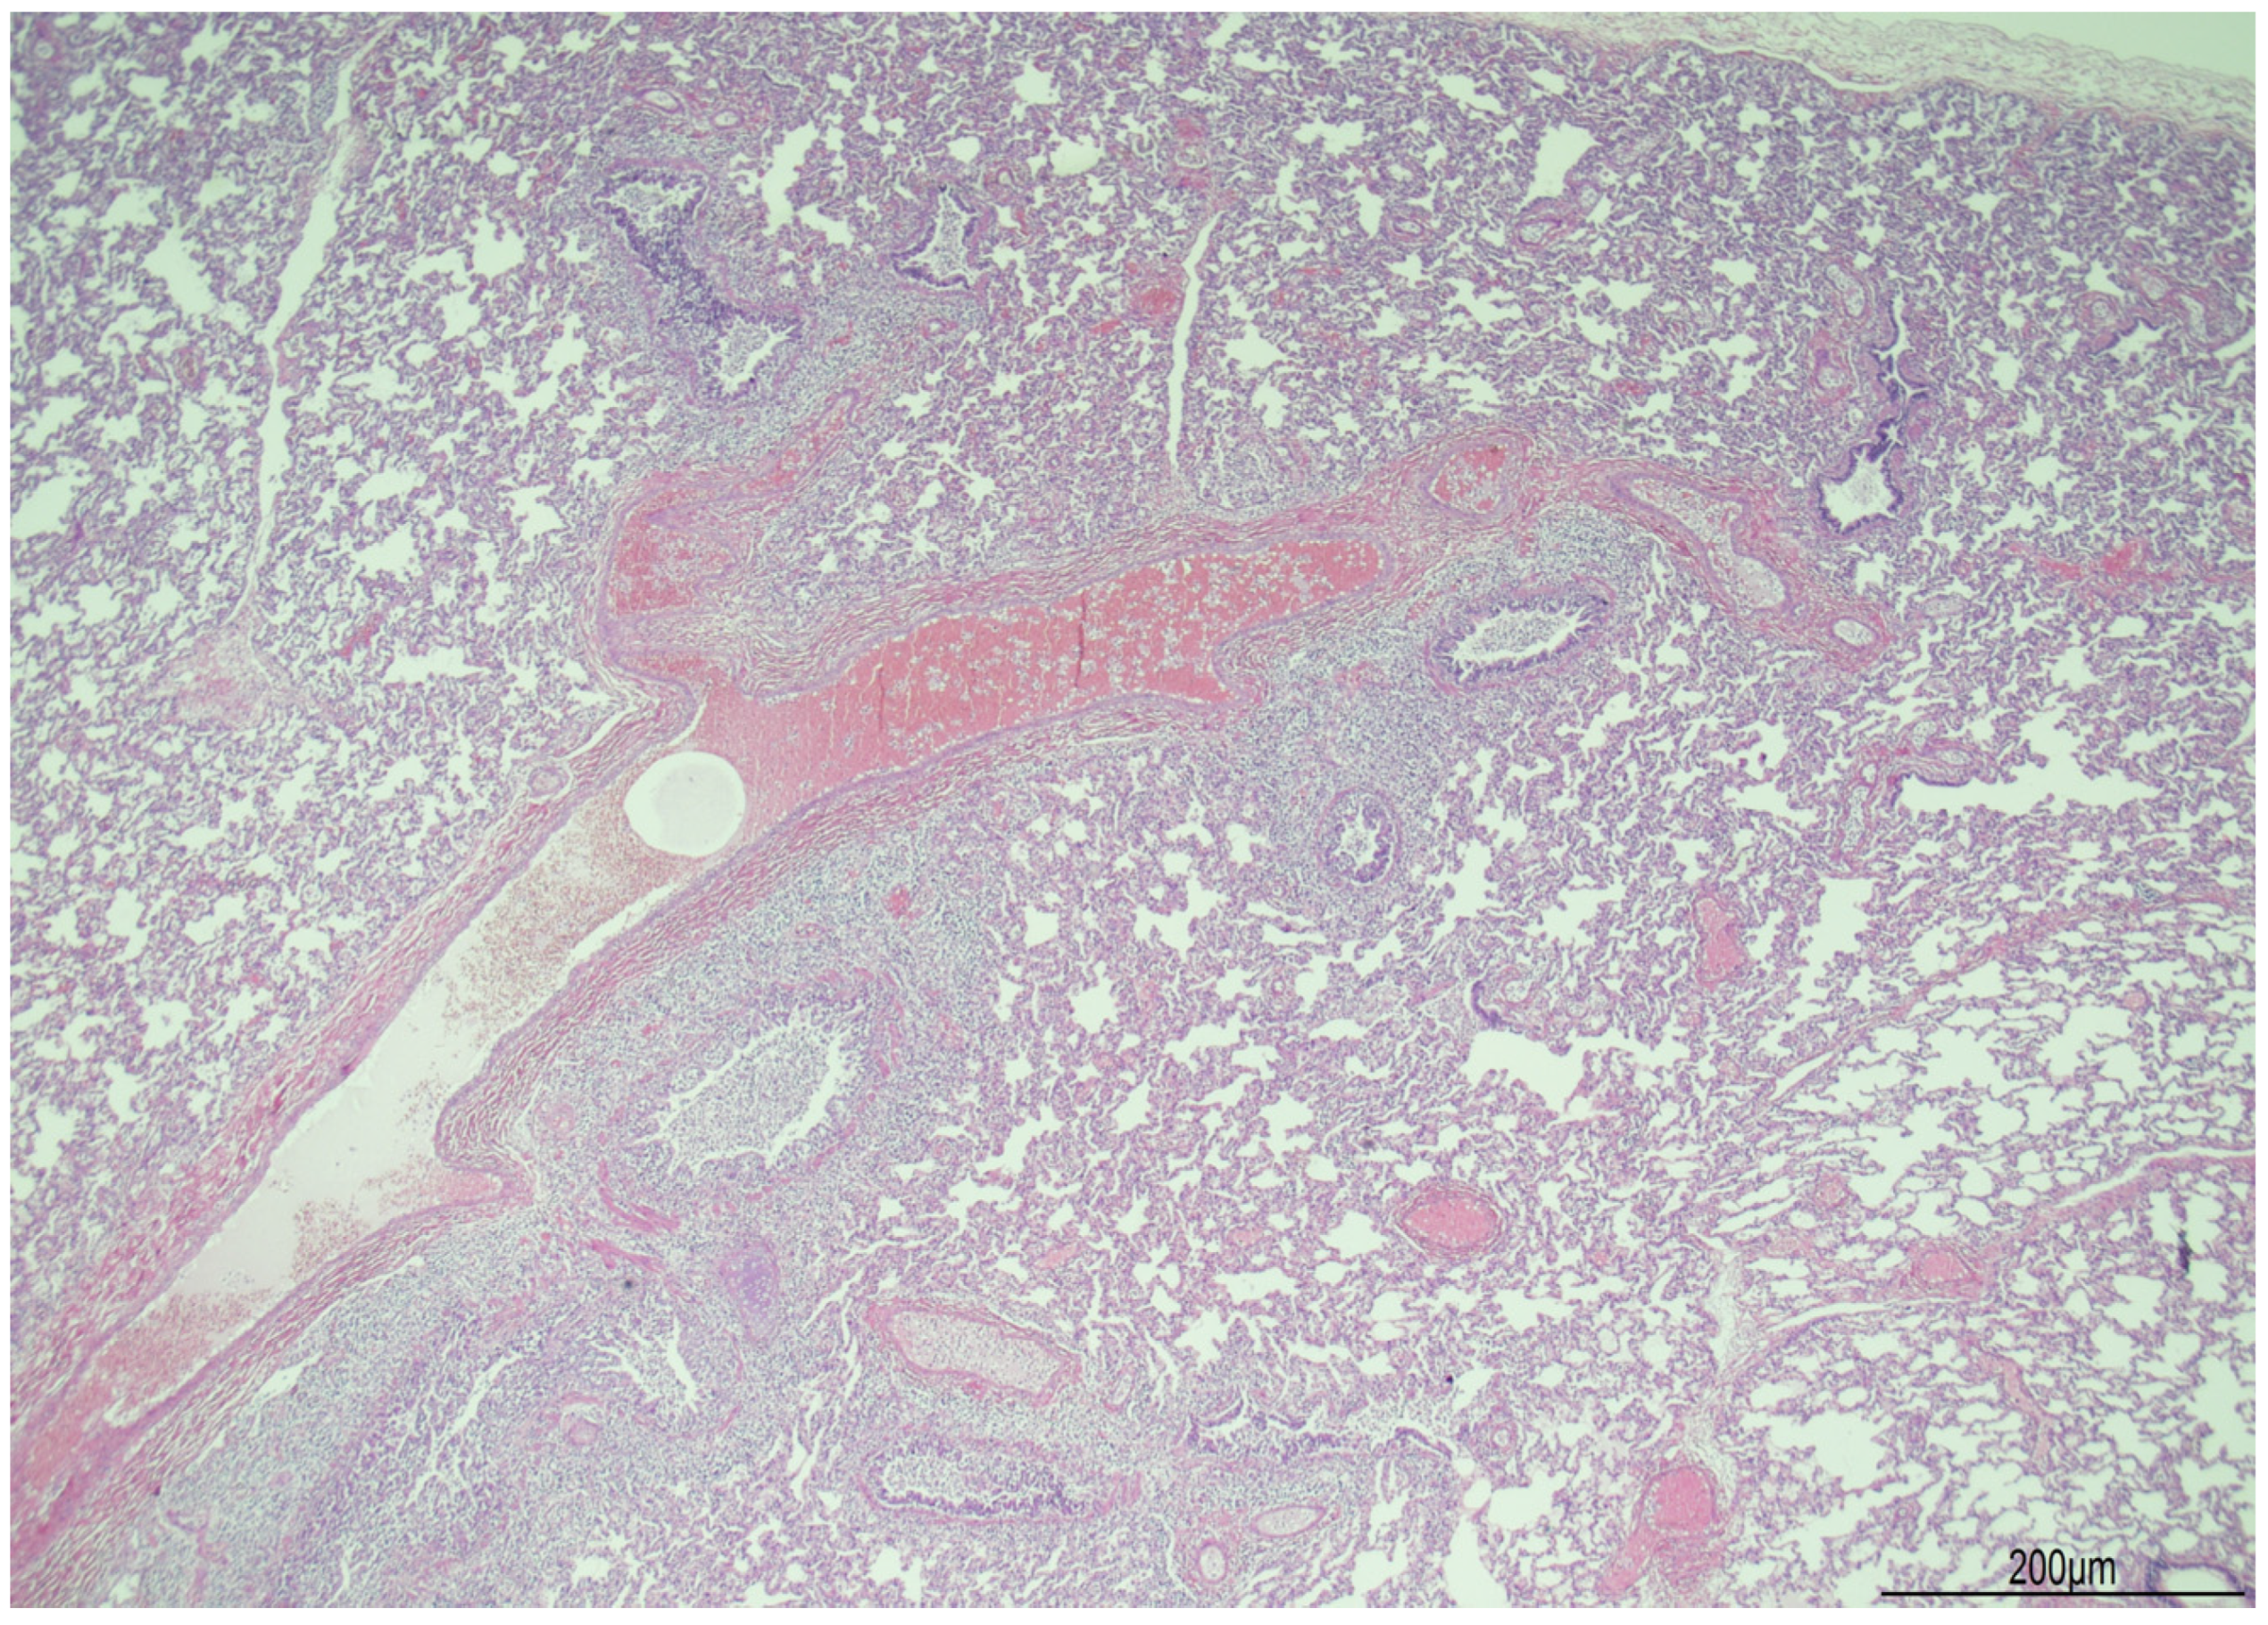

2.2. Autopsy Findings

2.3. Histological Findings